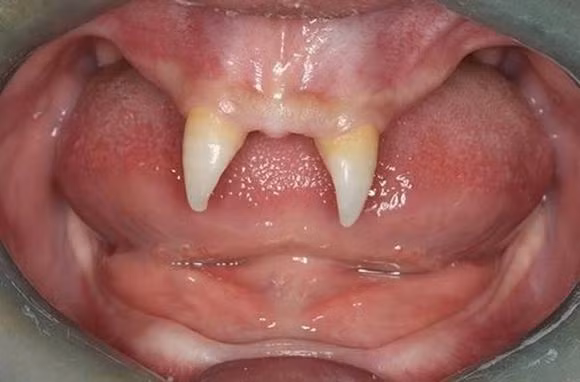

Mọc răng ma cà rồng

Một cậu bé Trung Quốc đã mọc 2 chiếc răng sắc nhọn ở hàm trên như ma cà rồng. Trong tháng 12/2012, mẹ Wang Hui đưa con trai Wang Pengfei, 16 tuổi, đến một bệnh viện địa phương để kiểm tra y tế. Cậu bé đến từ thành phố Trùng Khánh, phía tây nam Trung Quốc, có rất ít tóc lúc mới sinh và chỉ có hai chiếc răng nanh sắc nhọn trong miệng.